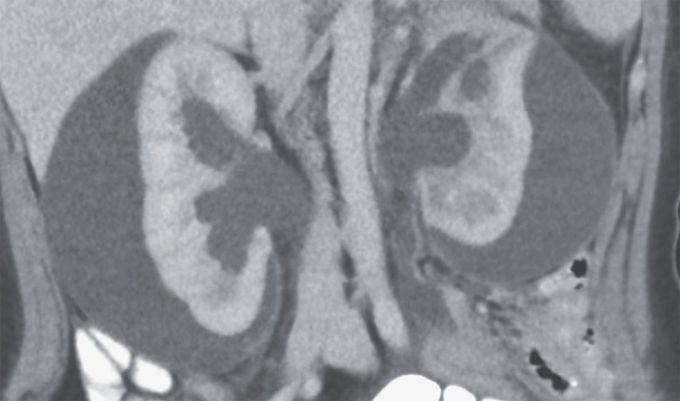

A 21-year-old woman presented to the emergency department with a 6-week history of abdominal pain and constipation. Her blood pressure was 162/108 mm Hg. She had a history of Hirschsprung’s disease and had undergone a partial colectomy and pull-through procedure during infancy. She had no history of hypertension or renal disease and reported no recent flank pain or hematuria. No abdominal or costovertebral-angle tenderness was present on physical examination. The serum creatinine level was 3.6 mg per deciliter (320 μmol per liter; reference range, 0.6 to 1.0 mg per deciliter [50 to 90 μmol per liter]). Computed tomography of the abdomen and pelvis revealed large subcapsular urinomas on both sides and hydronephrosis caused by distal ureteral obstruction from a rectal mass. After percutaneous drainage of the urinomas, the patient’s blood pressure normalized, which confirmed the diagnosis of secondary hypertension due to external compression of the renal parenchyma. This phenomenon, known as Page kidney, occurs when outer pressure on one or both kidneys impedes renal blood flow and results in increased renin secretion. The patient underwent ureteral stenting and biopsy of the rectal mass; histologic testing showed mucinous rectal adenocarcinoma. She was referred to the medical and surgical oncology departments for further treatment.